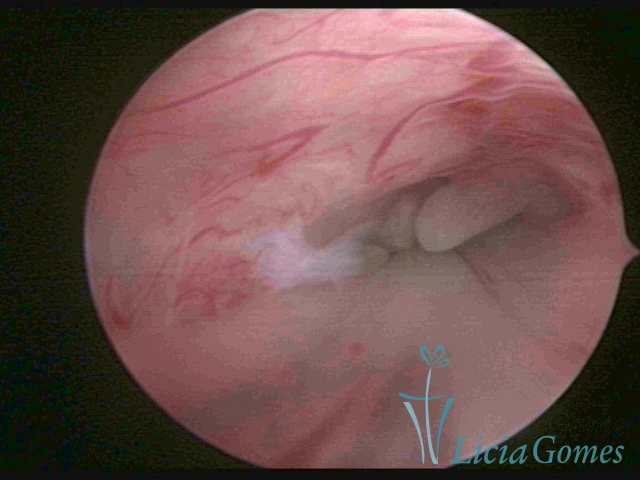

PÓLIPOS ENDOCERVICAIS

São tumores benignos, resultantes da proliferação focal reativa aos processos inflamatórios ou à situações de hiperestrogenismo, e podem ter sésseis (com a base de implantação larga) ou pediculados do epitélio.